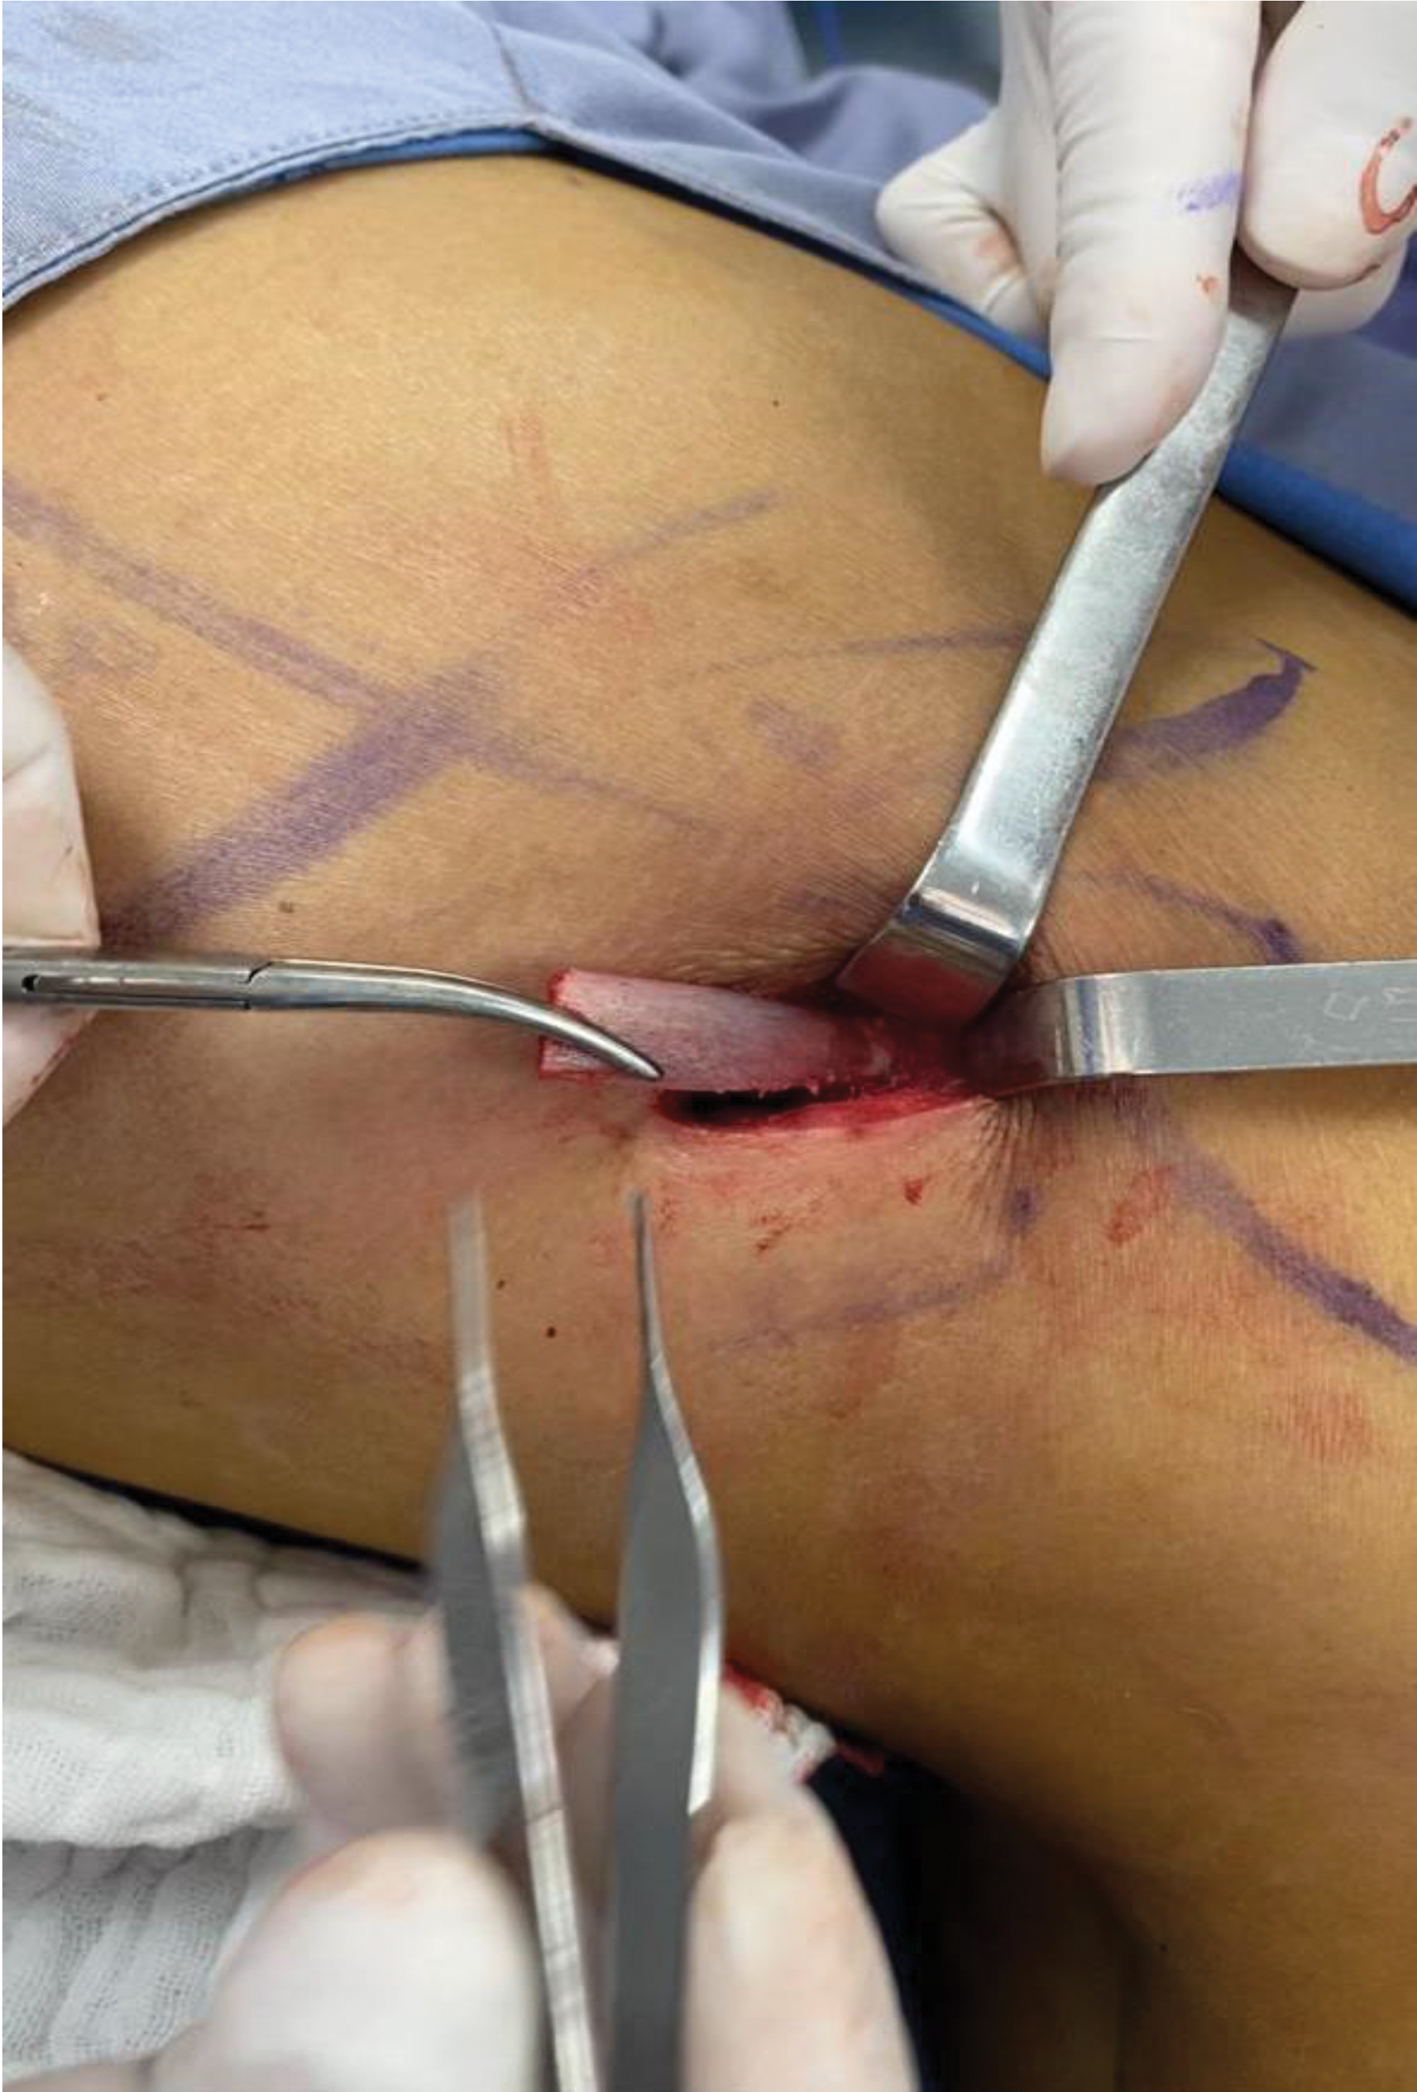

For the surgery, patients were placed in lateral decubital, aligning the waist to the axis of the table. In order to perform the subperiostic rib removal, an incision of 2.5 cm was made behind the posterior axillary line (Fig. 1), following the lower edge of the 11th rib and forming an acute angle between the incision line and the posterior axillary line. An incision of subcutaneous cell tissue was made, respecting the muscle fascia. A layered dissection was performed on the outer face of the rib, avoiding the intercostal area. For muscle avulsion, the aponeuretic fascia was taken with Adson forceps, and an atraumatic dissection was executed in the direction of the muscle fibers. When the periosteum was on sight, we began lateral and medial avulsions of the muscles until wide visualization of the rib was achieved (Fig. 2a, b). The periosteum was elevated by 7 mm chisel snuff until deperiostization of the exposed surface.

Fig 1

Fig. 1. 2.5 cm incision. The orifice above is from the liposuction’s approach port.

Fig 2

Fig. 2. (a) Eposed periosteum. (b) Visualization of the periosteum using Farabeuf retractors.